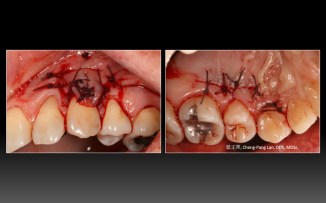

Root Coverage – Double Pedicle Graft – Case A

Recipient Site: Harris’s technique, 1992

Donor Site: Bruno’s technique, 1994